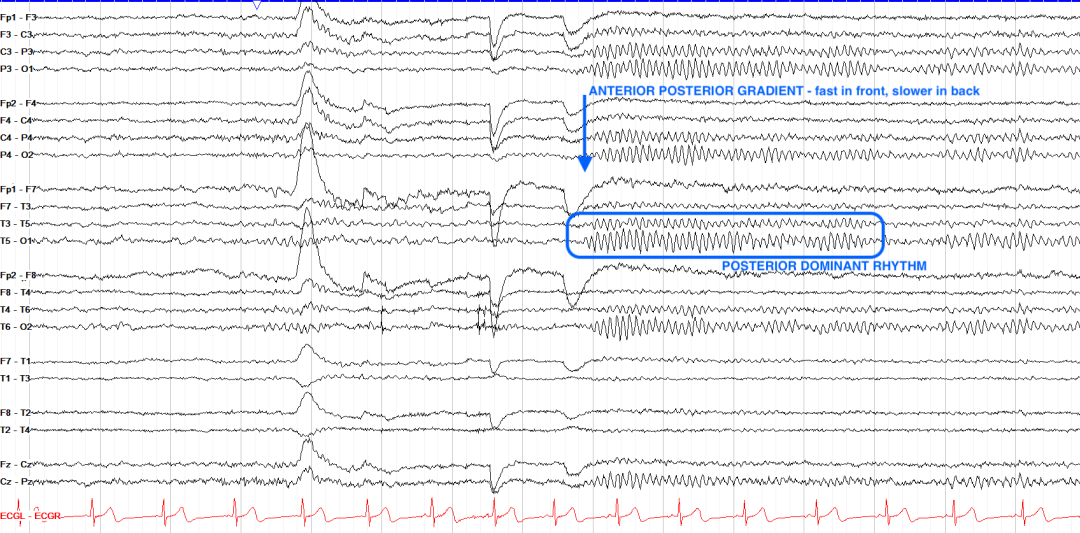

后部主导节律(PDR)是闭眼静息时枕叶区域的静息频率,正常范围8.5 - 12Hz,在α节律范围内,也被认为是α节律。

空间分布:优势分布于枕区(O1/O2导联),闭眼时波幅最高(20-100 μV),睁眼或注意力集中时被抑制(α阻断现象)。

•频率范围:13-30 Hz,主要分布于额区、中央区,与警觉状态、思维活动相关。

3.前后梯度

前额区以低幅快波(β活动)为主,后枕区以高幅慢波(α节律)为特征。梯度消失(如全脑弥漫性慢波)提示广泛性脑损伤或代谢性脑病。